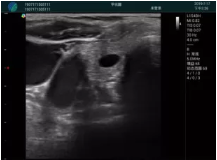

M20實(shí)時(shí)引導(dǎo):向包塊后方間隙注射利多卡因

清晰顯示腺體內(nèi)低回聲快影,邊界清晰,包膜較光滑

確定進(jìn)針路徑并實(shí)時(shí)監(jiān)測(cè)抽吸針與腫塊位置關(guān)系

抽吸針進(jìn)入腫塊內(nèi)部進(jìn)行旋切

抽吸過(guò)程中可見(jiàn)腫塊明顯縮小,并根據(jù)腫塊位置改變針道位置

抽吸旋切后再進(jìn)行超聲復(fù)查,原腫塊區(qū)域未見(jiàn)殘留組織及出血

超聲引導(dǎo)下抽吸旋切取出的腫塊組織